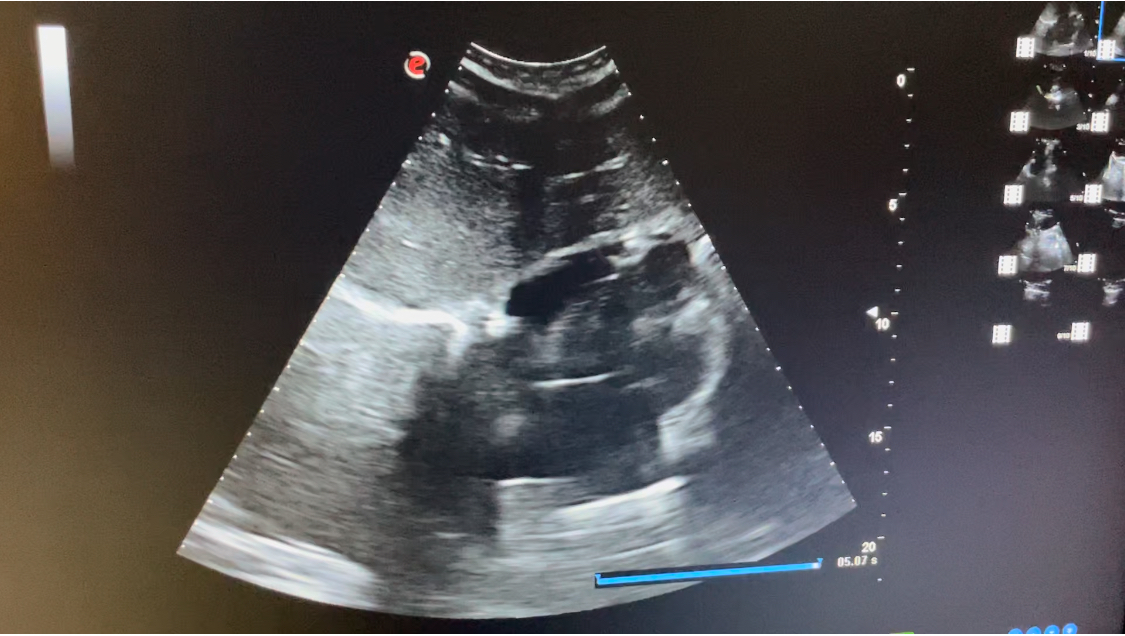

Estudio ecográfico con sonda abdominal de baja frecuencia, siguiendo protocolo ECO-FAST. Se explora región subxifoidea sin apreciarse presencia de líquido en saco pericárdico. Hipocondrio derecho libre de líquido en espacio de Morrison. Hipocondrio izquierdo sin presencia de líquido en espacio esplenorrenal. Imagen de región supra púbica, corte longitudinal y transversal donde no se observa líquido libre en saco de Douglas.